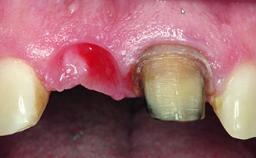

A 32-year-old female Caucasian patient with a compromised maxillary right central incisor was referred to us by a general dentist. Her chief complaints were discomfort and mobility of tooth 11 with unsatisfactory esthetics due to discoloration. The patient reported a previous trauma, some years earlier, as the origin of pathology on the afflicted tooth. Anamnesis was negative for any other dental or periodontal pathology in the remaining dentition. The patient did not take any medication and reported to be a light smoker (5–10 cigs/day). She had high esthetic expectations of her treatment. The extraoral examination revealed a high smile line with full exposure of her maxillary teeth and surrounding soft tissue in the area between the second premolars.

Soft Tissue Anatomy Intact Defective

Soft Tissue Contour and Volume Slightly compromised